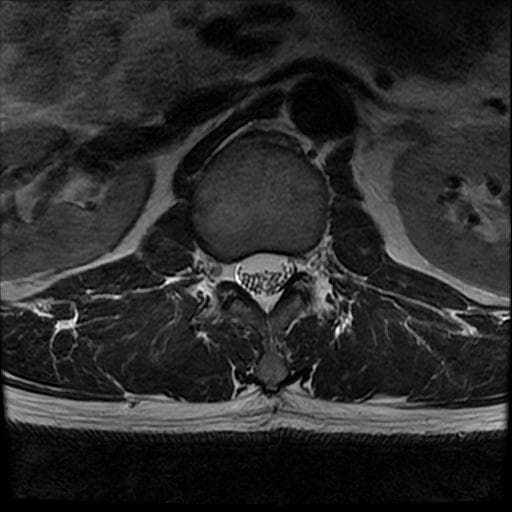

이번에 허리 MRI찍었는데

상태 어떤지 고견 여쭙습니다.

큰 이상이나 문제점은 없어 보이는 것으로 생각되는데요, 허리통증이 지속되는 경우에는 반드시 디스크 질환에 의한것은 아닐 수 있습니다.

현재로썬 디스크 상태는 심하지않는것으로 확인이 됩니다.

MRI 영상 커트로 판독을 할 수는 없습니다.